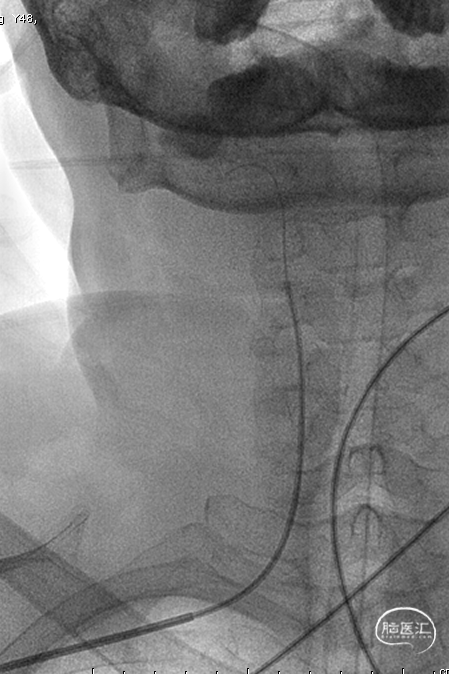

右侧桡动脉穿刺造影:右侧椎动脉优势;左侧椎动脉发自弓上,纤细迂曲;双侧后交通动脉欠发达。

超选右侧椎动脉造影:右侧椎-基底动脉连接处次全闭塞,前向血流 mTICI 2b级。

气管插管全麻。6F 指引导管、5F多功能管、泥鳅导丝同轴,将指引管放置于右侧椎动脉V2段。路径图下,将Synchro-14 微导丝引导SL-10微导管导管小心通过椎基底动脉次全闭塞处,放至右侧大脑后动脉P1段。更换为Trensend-300cm微导丝,撤出SL-10微导管。